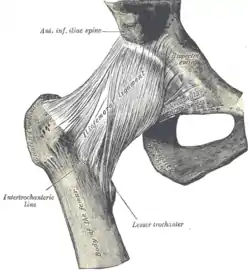

Ligaments

The hip joint is reinforced by four ligaments, of which three are extracapsular and one intracapsular.

The extracapsular ligaments are the iliofemoral, ischiofemoral, and pubofemoral ligaments attached to the bones of the pelvis (the ilium, ischium, and pubis respectively). All three strengthen the capsule and prevent an excessive range of movement in the joint. Of these, the Y-shaped and twisted iliofemoral ligament is the strongest ligament in the human body. It has a tensile strength of 350 kg.[22] Iliofemoral ligament is a thickening of the anterior capsule extending from anterior inferior iliac spine to intertrochanteric line.[5] Ischiofemoral ligament is the thickening of posterior capsule of the hip and pubofemoral ligament is the thickening of the inferior capsule.[5] In the upright position, iliofemoral ligament prevents the trunk from falling backward without the need for muscular activity, thus preventing excessive hyperextension. In the sitting position, it becomes relaxed, thus permitting the pelvis to tilt backward into its sitting position. Ischiofemoral prevents excessive extension and the pubofemoral ligament prevents excess abduction and extension.[24]

The zona orbicularis, which lies like a collar around the most narrow part of the femoral neck, is covered by the other ligaments which partly radiate into it. The zona orbicularis acts like a buttonhole on the femoral head and assists in maintaining the contact in the joint.[22] All three ligaments become taut when the joint is extended - this stabilises the joint, and reduces the energy demand of muscles when standing.[25]

Hip joint. Lateral view.

Hip joint. Lateral view. Hip joint. Lateral view.